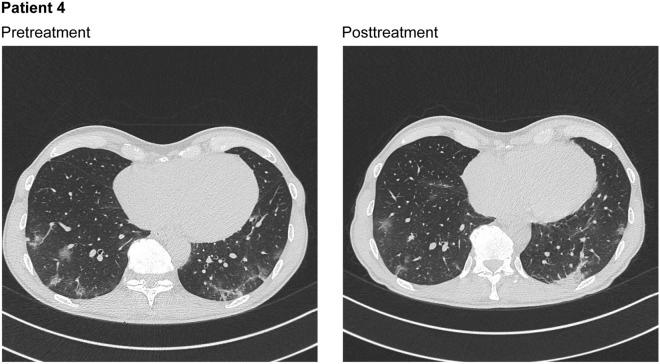

Ribavirin is an inosine monophosphate dehydrogenase inhibitor with demonstrated activity against coronaviruses, including SARS-CoV-2. Five hospitalized patients with COVID-19 (confirmed by positive tests for SARS-CoV-2) received treatment with ribavirin for inhalation solution (ribavirin aerosol) as part of a compassionate use program. Patients included four men and one woman, with an age range of 29-72 years. Patients were managed according to international and Italian treatment guidelines for COVID-19. In addition, therapy with ribavirin aerosol 100 mg/mL was administered for 30 min twice daily for 6 days (i.e., 12 doses) in all patients. In order to address concerns about a possible increase in viral dispersal with the use of a nebulizer, healthcare providers remained outside the patient room during ribavirin aerosol administration. Pretreatment chest computed tomography (CT) scans showed pseudonodular areas of parenchymal thickening in the upper right lobe with associated ground glass opacities, multiple areas of parenchymal consolidation in both lower lobes with associated ground glass opacities, bilateral parenchymal thickening and multiple associated ground glass areas, or focal ground glass areas in the upper lobes bilaterally, which were almost completely resolved (three patients) or moderately cleared (one patient) on imaging at the end of ribavirin treatment. For a fifth patient, CT scans showed a stable pulmonary picture at the end of ribavirin treatment. No adverse reactions to ribavirin treatment were observed in any of the five patients. All patients recovered fully, and nasopharyngeal swabs obtained after hospital discharge tested negative for SARS-CoV-2. Ribavirin aerosol appears to be efficacious in the treatment of patients with COVID-19. A controlled trial of ribavirin aerosol is ongoing and will provide additional data across a broader patient population.